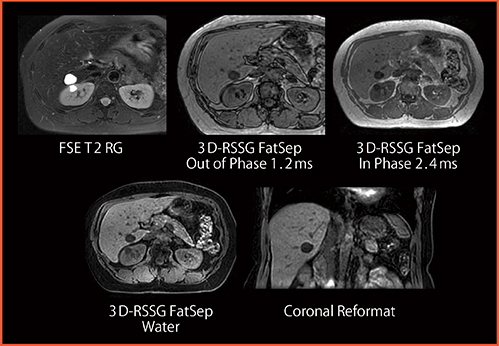

続いて,MRIシステム本部クリニカルサイエンスグループの原田邦明氏が「3T MRIの画像について」と題し,3T MRI「TRILLIUM OVAL」の画像を多数供覧した。4ch RFシム技術,2 Point Dixon法,非造影MRA,3D FSE(isoFSE),μTEなどの先進技術による高精細画像をはじめ,開放的なOVALのガントリ形状を生かした肩関節や股関節,膝関節などのポジショニングの特徴について解説した(図1〜5)。

図1 4ch RF シム技術:尿管癌の2D FSE RG

(FOV38cm,5mm,3min)

3T MRIで課題であった腹部においても,4chのシミング効果で適正なRF送信が可能となり,良好な描出能が得られている。

(画像提供:岩手医科大学附属病院)

図2 2 Point Dixon法(2mmスライス,息止め19s)

脂肪抑制のin phase,out of phase,水画像すべてを1回で撮像する。

コロナル画像に再構成しても診断に十分な精度が得られている。